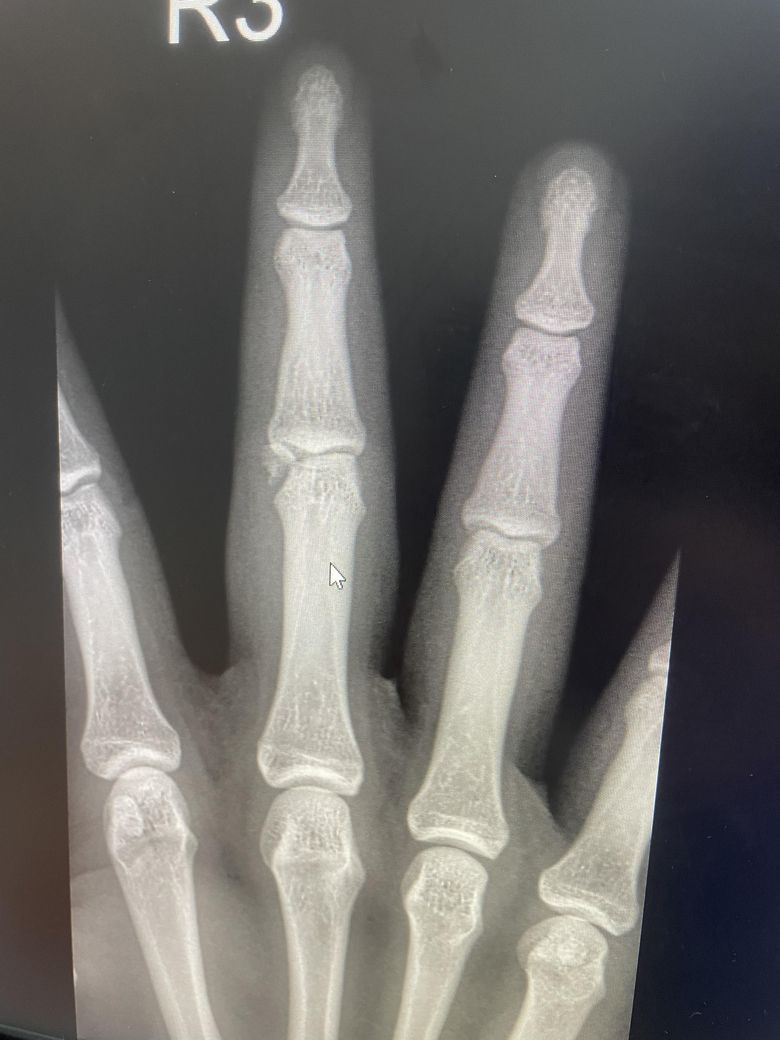

운동선수 손가락골절후 뼈이식 재수술질문이요!

안녕하세요 제가 올해2월에 손가락이 부러져서 핀 2개박는 수술을 하였습니다 그러나 뼈가 붙지않아서 이번에는 뼈이식 수술을 한다고 하는데요 만약 하게 된다면 운동 복귀는 언제쯤 될까요?(럭비선수입니다!)

• 1번 째 사진

뼈 이식 후 손가락 골절은 보통 6~8주 내 유합 운동 복귀는 3개월 전후로 예상됩니다. 럭비처럼 충격이 큰 종목은 기능회복+재골절 방지를 위해 4개월 이상 걸릴 수도 있습니다 회복속도는 이식 범위 고정 안정성 재활 노력에 따라 달라집니다 정형외과 전문의와 스포츠재활팀의 단계별 복귀 계획이 꼭 필요합니다!